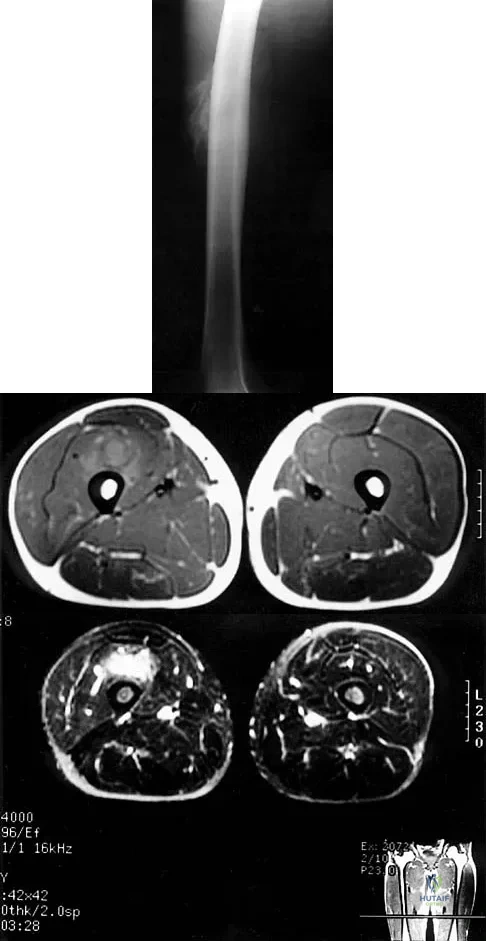

Figures 8a through 8c show the lateral radiograph and T1- and T2-weighted MRI scans of a 14-year-old soccer player who reports aching thigh pain. The next most appropriate step in management should consist of

Explanation